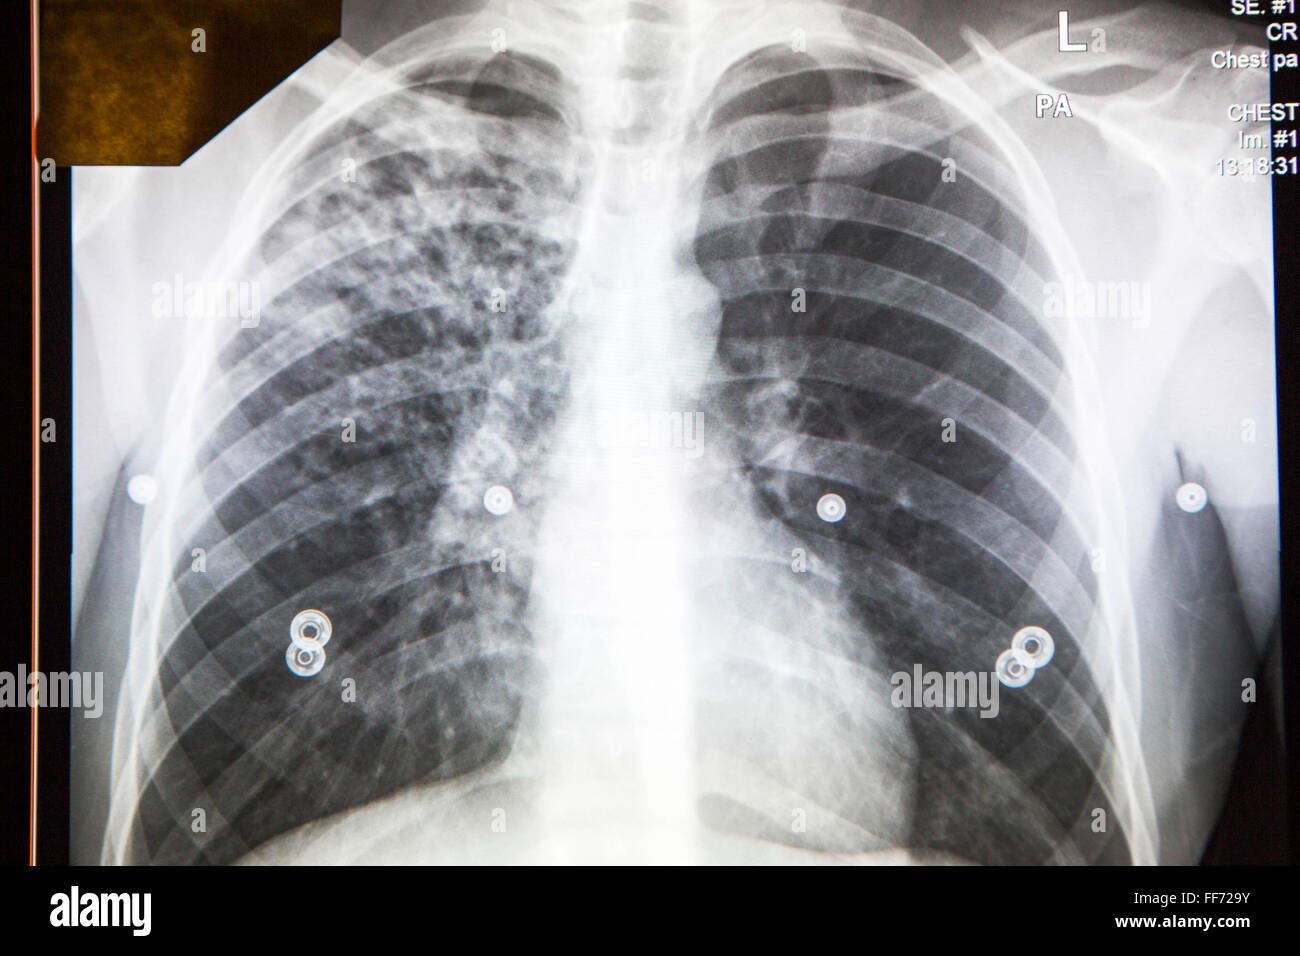

Imagen: En este rayo x de tórax de un paciente con sintomatología respiratoria, donde se observa una tremenda caverna que es un hueco, generalmente tienden a localizarse hacia los ápices pulmonares.

Tenemos otra imagen de un paciente con TBC bronconeumónica. Vamos a buscar las diferencias: fíjense que la TBC cavitaria generalmente afecta a un solo pulmón y se ve una caverna. Mientras que la forma bronconeumónica es un infiltrado difuso del parénquima pulmonar que va desde la superficie hasta la base, desde la parte más interna hasta la parte más externa, pero es un infiltrado algodonoso. Ojo esto puede ser causado por una bronconeumonía de otra etiología, para confirmar si es TBC debemos hacer biopsia.